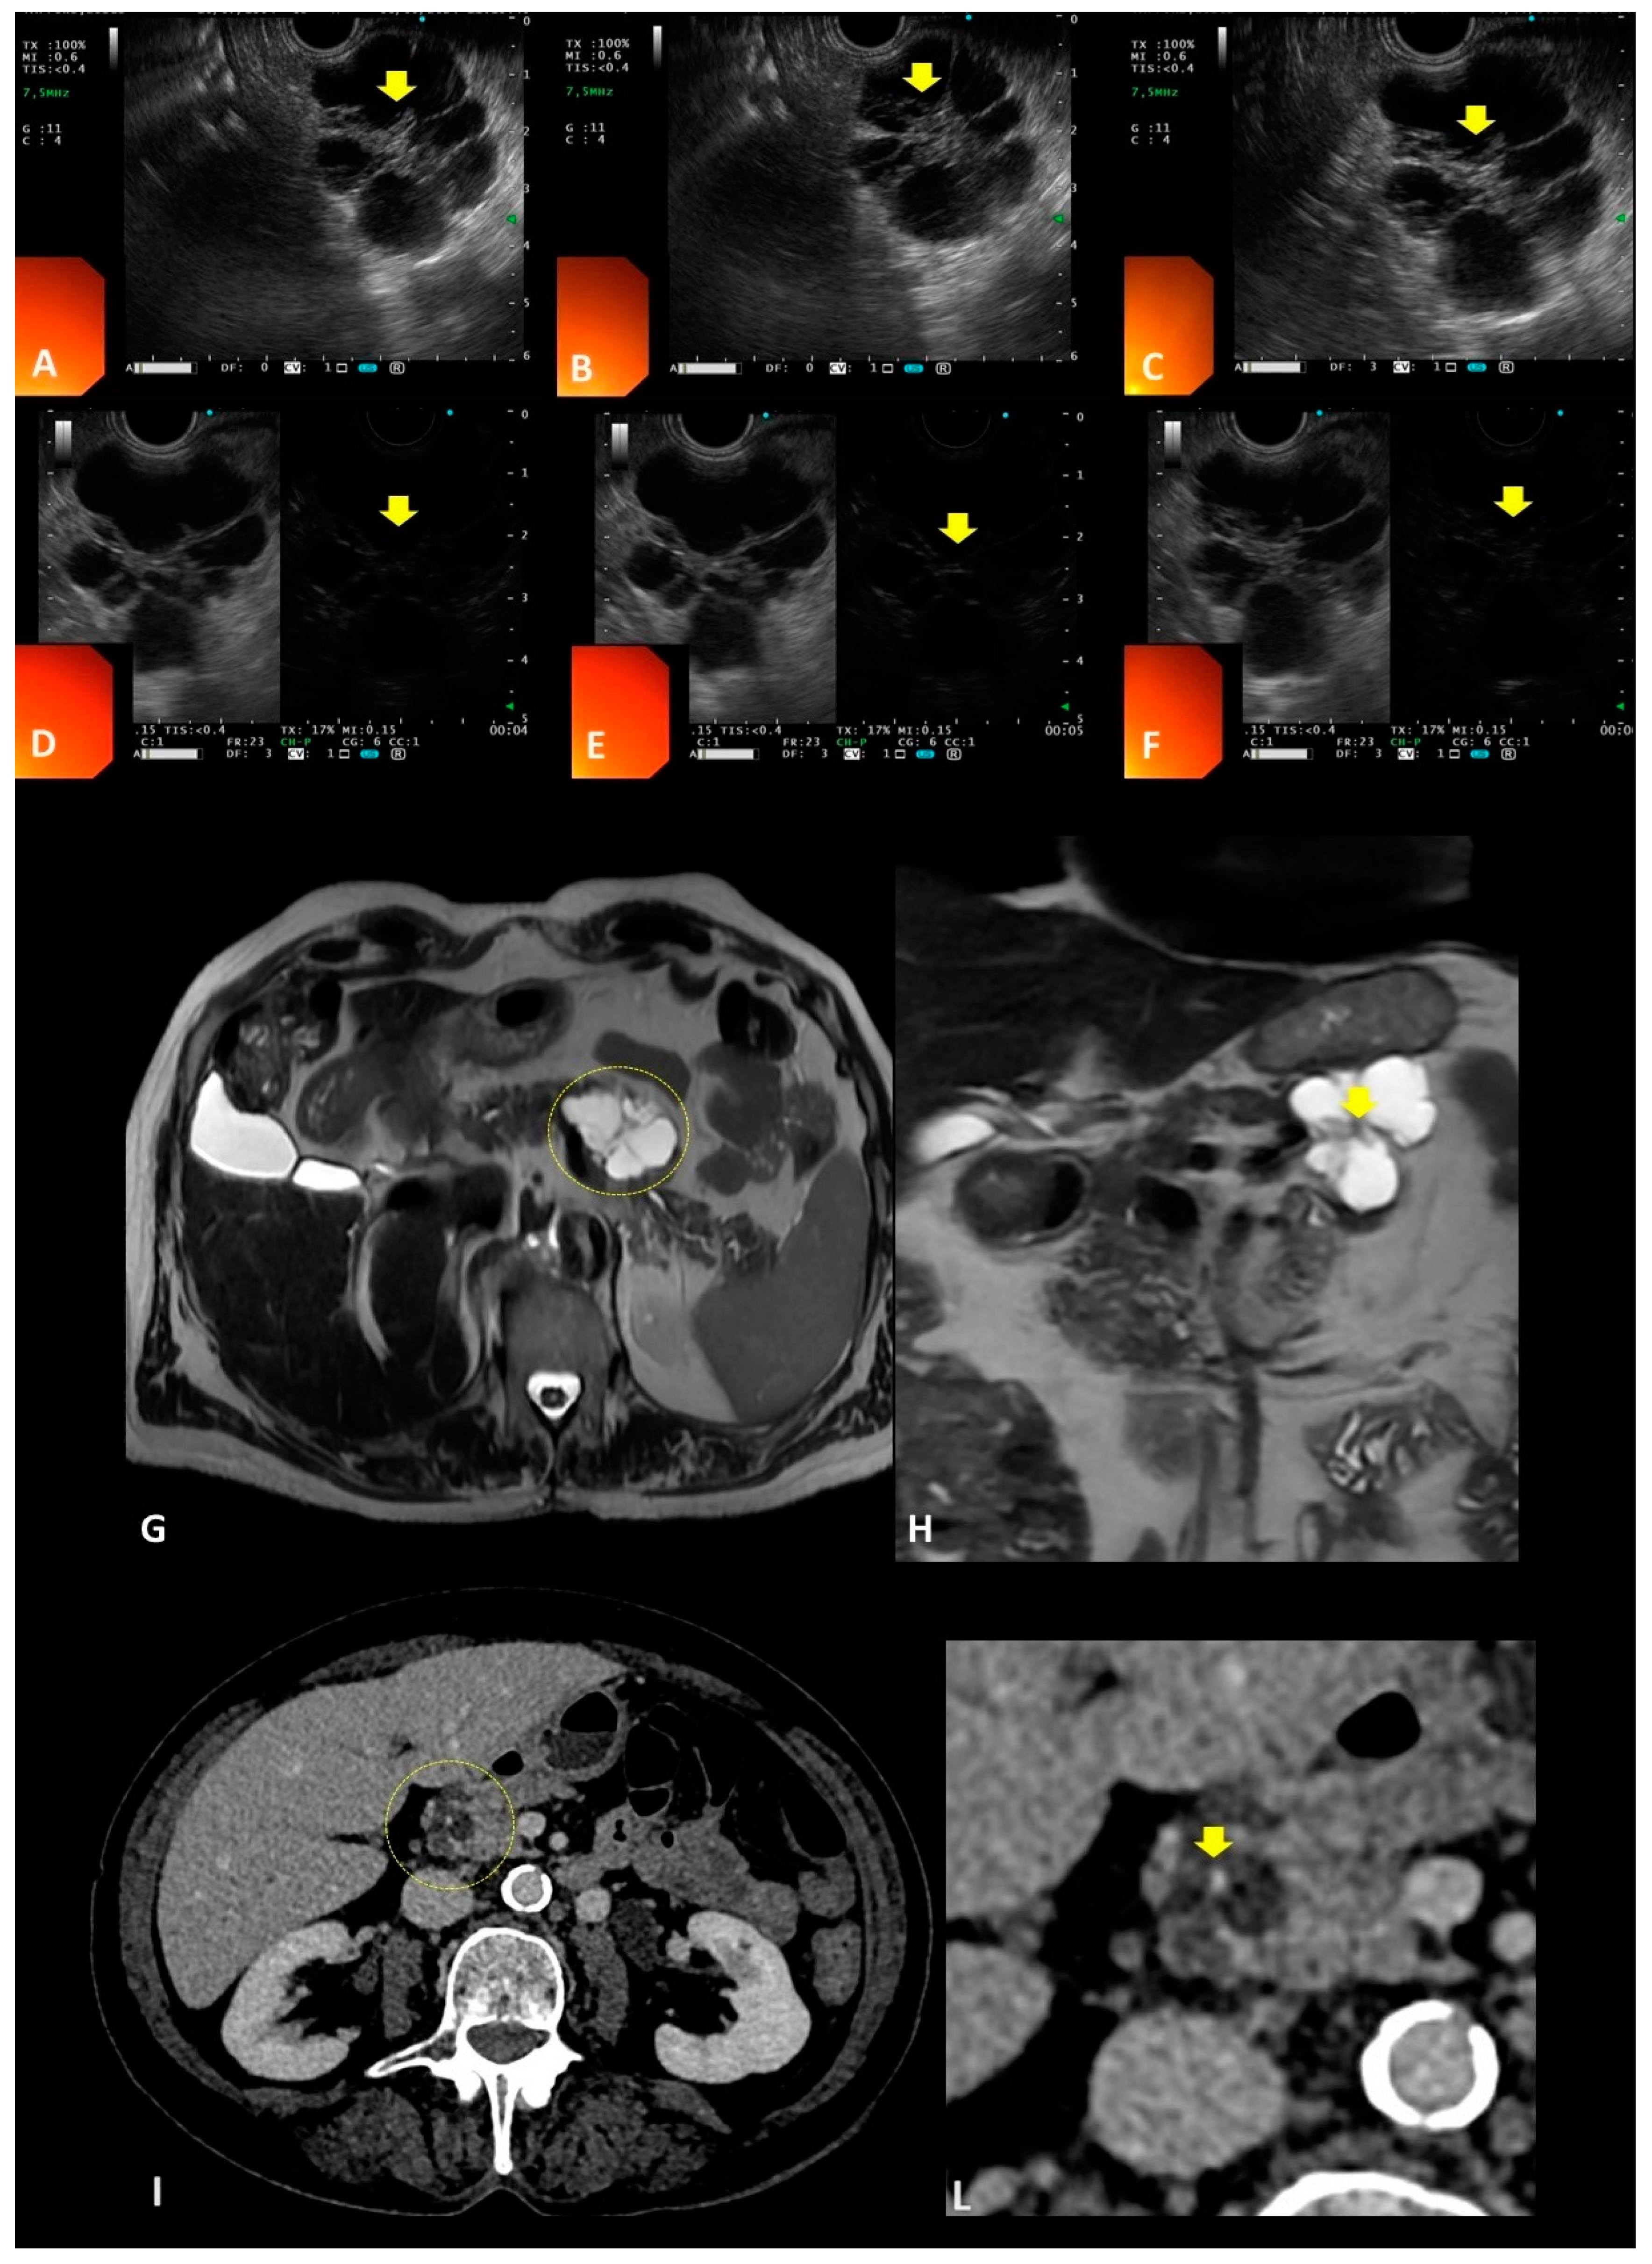

| Central stellate scar | SCN | Imaging (CT, MRI, EUS) | - 20–30% of cases - May be calcified or non-calcified - Best assessed by CT |

| Chylous cyst fluid with high triglyceride levels | CL | EUS-FNA and cyst fluid analysis | - When not present, a certain diagnosis is difficult and surgery may be needed |